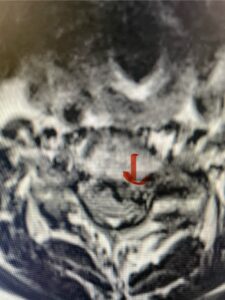

The case illustrates a more subtle finding of cervical myelopathy in a young 52 year-old male who presents with 5 months of left upper extremity weakness and burning. He also had developed over the last two months pain in his right upper extremity. He also had difficulty with fine motor skills. He had a positive Hoffman reflex and mild 4-4+ long tract weakness of his left arm and leg. Cervical MRI revealed an explanation for the patient’s symptoms (Fig. 7) as it revealed a disc osteophyte complex causing some cord flattening, slightly more to the left. We performed a C5-6 anterior cervical discectomy and interbody fusion with cage and plate (Fig. 8) He had a significant improvement in his weakness, numbness, and pain. What is interesting is that this was a relatively young patient without severe cord compression but was significantly affected by a mild amount of cord compression. This may speak to how a younger spinal cord may react much more adversely perhaps secondary to a less compliant spinal cord.

Fig. 7a Sagittal and axial T2-weighted cervical MRI’s demonstrating spinal cord compression slightly to the left secondary to disc/osteophyte complex (red arrow)

Fig. 7b